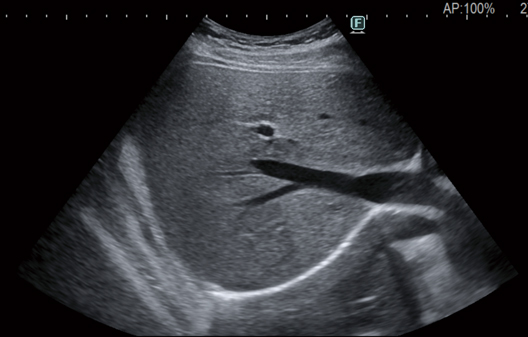

The eFocusing transmission and reception technology newly developed for ARIETTA 850, significantly improves S/N and reduces focal dependency. Outstanding clarity of imaging from near to far field with less patient dependency is achieved.

Focused at all depths

Advanced image technology producing images with "Clearer Visibility"*. Stable imaging with less patient dependency helps to achieve clearer images with less noise. This is made possible by our new image processing technology that enhances tissue structure visibility.